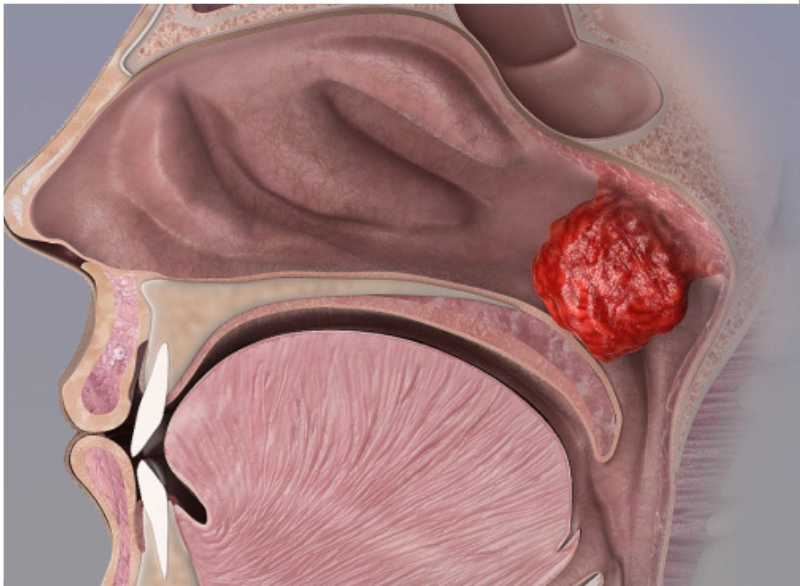

Adenoidectomy is the surgical removal of the adenoids—small lymphatic tissue located behind the nasal passage. When these become enlarged or infected frequently, they can block airways, cause snoring, breathing problems, and persistent ear or sinus infections.

- Enlarged adenoids

Under general anesthesia, the adenoids are removed through the mouth—no cuts on the outside. The procedure takes less than an hour.